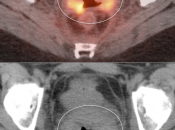

Cervical Cancer

Initial Staging:

- Valuable diagnostic tool for locally advanced disease, to determine nodal status and potential distant metastatic disease (if no evidence of regional or distant disease, initial management is surgical).

- PET/CT has high sensitivity (>80%) and high specificity (>90%) for metastatic lymph nodes ≥ 8.0 mm.

What We Report:

The size, metabolic activity & location of the primary lesion and representative metastatic lesions are reported.

Primary Lesion:

- Nearly every cervical cancer ≥ 8.0 mm is intensely FDG avid (MRI, however, is still considered the best modality for evaluating tumor size and invasion).

Metastatic Disease:

- Direct invasion of adjacent structures.

- Lymphatic spread to pelvic and retroperitoneal lymph nodes.

- Hematogenous spread, often to lungs, liver, and bone.

False Negatives:

- Primary lesions < 8.0 mm (beneath the resolution of PET)

- Nodes or metastatic deposits < 8.0 mm

False Positives:

- Post-radiation inflammatory changes